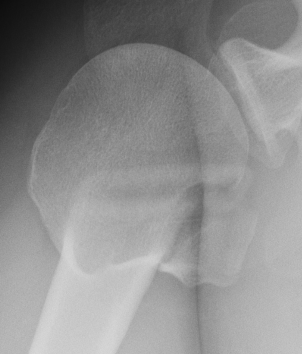

Three part

Three part with greater tuberosity fracture

Three part fracture dislocation anterior

Three part fracture dislocation with anatomical neck

Three part head splitting fracture